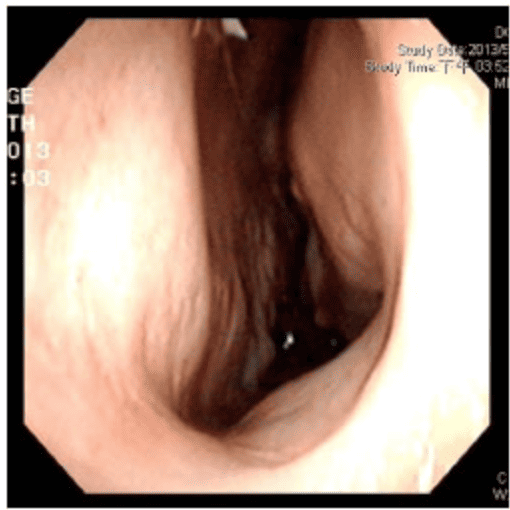

▲透過手術前後鼻阻力圖對照,術前右側鼻阻力線都接近水平線,表示呼吸阻力極大,術後鼻阻力線恢復正常曲線,接近兩邊對稱,表示呼吸恢復暢通,傷口也恢復良好。